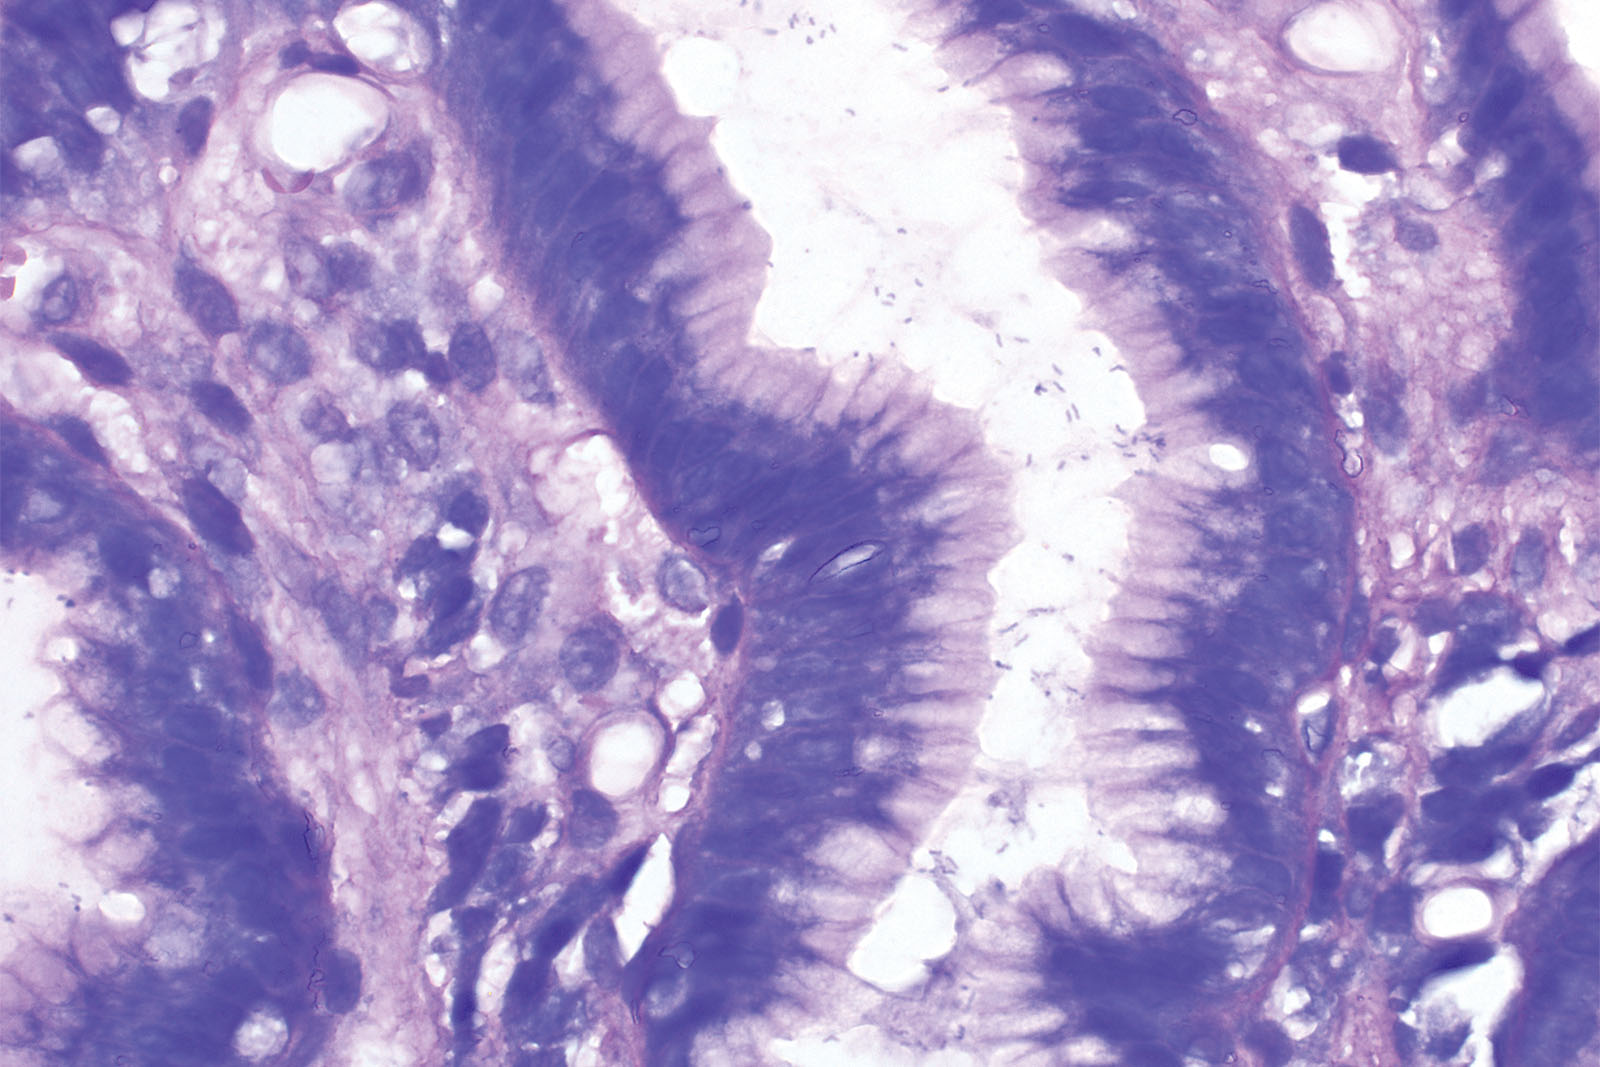

Polychromatic Romanowsky dyes are a standard in hematology of blood smears and bone marrow. Giemsa is one of the Romanowsky dyes and beside hematology, it can be used in histology for visualization of Helicobacter pylori in gastroscopic samples of the stomach. This staining method is also known as slow Giemsa staining according to Lennart. Giemsa solution may also be used to identify blood parasites, inclusion bodies and mastocytes in histology sections. Giemsa HP kit for 100 tests contains reagents for differentiation and rehydration in Ready-to-Use jars, enabling the sections to be directly immersed during the staining procedure. The jars are closed after the use, and reagents can be reused.